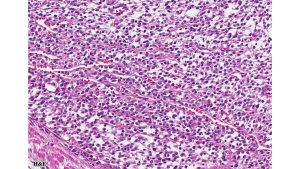

Histologic examination revealed densely cellular fascicles of monomorphic spindle cells with indistinct borders, oval nuclei and scant cytoplasm. The background showed necrosis and areas of hemorrhage. Immunohistochemical analysis revealed tumor cells positive for vimentin, CD99, BCL-2 and TLE1, while negative for CEA, EMA, desmin, chromogranin, synaptophysin, enolase, S-100, CD10, CD117, Caldesmon, beta-catenin, PAX2, and WT-1.

Primary synovial sarcoma of the kidney is exceedingly rare and often presents a diagnostic challenge due to morphologic overlap with other renal spindle cell tumors, such as sarcomatoid renal cell carcinoma, sarcomatoid urothelial carcinoma, and other primary renal sarcomas (e.g., leiomyosarcoma or malignant peripheral nerve sheath tumor). The monophasic spindle cell variant lacks epithelial components, making differentiation particularly difficult without molecular testing. Immunohistochemistry often demonstrates expression of TLE1, CD99, vimentin, and BCL-2, but these markers are not entirely specific. The definitive diagnosis hinges on detecting the characteristic t(X;18)(p11;q11) translocation, which results in the SS18-SSX fusion (typically SSX1 or SSX2) via FISH or RT-PCR.. These tumors tend to behave aggressively, with potential for local recurrence and distant metastasis, particularly to the lungs and liver. Long-term follow-up is essential, and optimal management often requires a multidisciplinary approach, incorporating surgery and consideration of systemic therapy in selected cases.